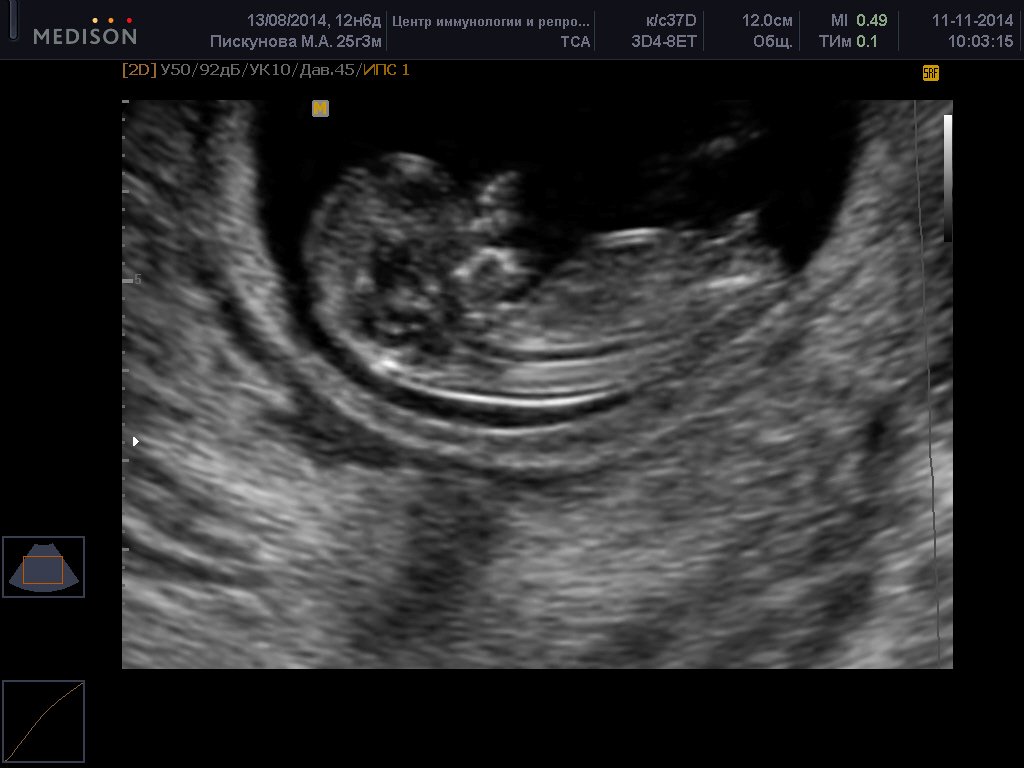

Первый скрининг при беременности нормы на фото:

УЗИ скрининг

Скрининговое УЗИ в первом триместре обычно занимает не более 30 минут. Если исследование проводится трансвагинальным методом, на датчик надевается одноразовый презерватив, после чего он аккуратно вводится во влагалище. При правильном выполнении процедуры беременная женщина не должна испытывать никаких неприятных ощущений.

При трансабдоминальном УЗИ передняя стенка живота будущей мамы обрабатывается специальным гелем. Датчик устройства перемещается по поверхности, а изображение выводится на экран. Это исследование также не вызывает дискомфорта у беременной.

Первый скрининг при беременности: расшифровка УЗИ на фото. Увеличение уровня РАРР-А в первом триместре не указывает на наличие хромосомных аномалий у плода. Однако снижение этого гормона может говорить о синдроме де Ланге, Дауна или Эдвардса. В некоторых случаях низкие показатели могут свидетельствовать о замершей беременности или угрозе самопроизвольного аборта.